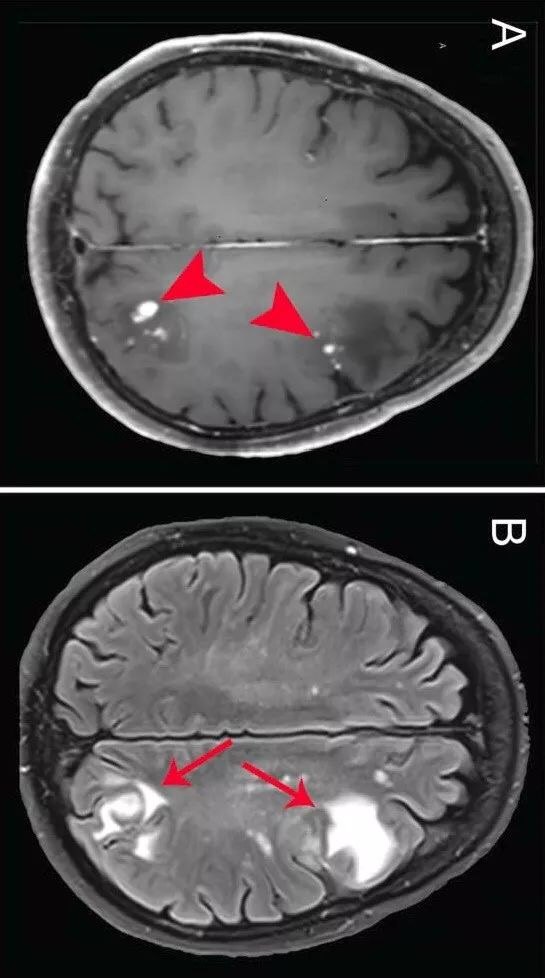

teaching neuroimages: neuroimaging in hemiplegic migraine.

图片尺寸499x556